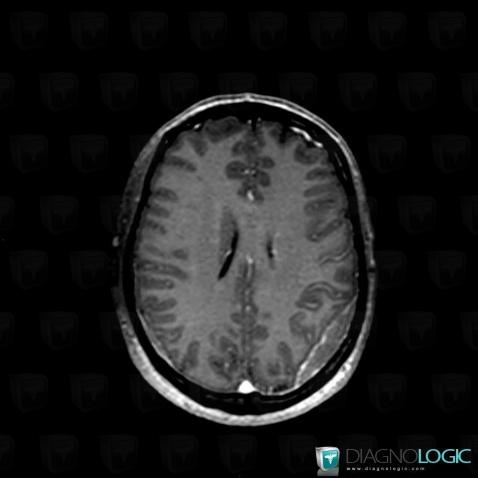

Voici les informations spécifiques à l'image clé ci dessus:

- Diagnostic Lymphome , Localisation(s) Espaces peri cérébraux supratentoriels, comportant les gammes Réhaussement méningé focal, Lésion extra axiale supra tentorielle